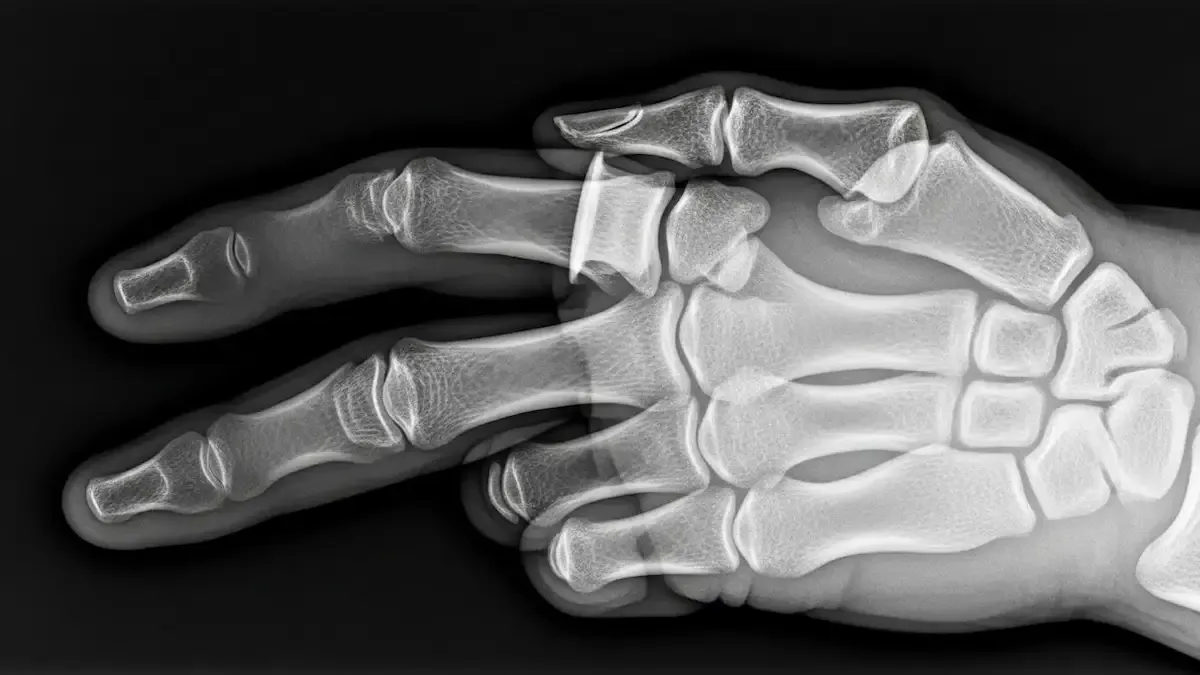

Como Saber Se Desloquei O Dedo Da Mão?

Lesões nos dedos são frequentes no consultório, principalmente após quedas, impactos ou atividades esportivas. Muitos dos meus pacientes ficam na dúvida: como saber se desloquei o dedo da mão? A luxação acontece quando os ossos da articulação saem...